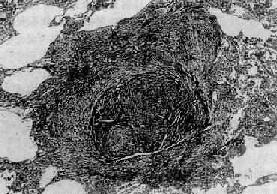

肺蟎病體徵

肺蟎病實驗室檢查:1.一般檢查外周血白細胞正常或輕度增加。嗜酸粒細胞常增高,約占10%~50%。血清IgE明顯增高,可達正常人的5~6倍。IgG和IgA也增高,IgM在疾病早期雖有不同程度增高,但與對照組比較無明顯差異。痰可有較多的嗜酸粒細胞。偶見夏科結晶。留24h痰經5%~7.5%氫氧化鈉消化2~3h,離心塗片鏡檢找到蟎成蟲、幼蟲或卵可確診。

2.免疫學檢查常用的有:(1)皮試:多用蟎變應原點刺試驗(SPT),其總陽性率達80%。(2)間接螢光抗體試驗(IFA):方法簡便,敏感性及特異性均較好,陽性率在90%以上。(3)間接血凝試驗(IHA):陽性率較IFA稍低,約85%,其特異性也較好,診斷肺蟎病時其滴度宜≥1∶16。(4)生物素-親和素酶聯免疫吸附(ABC-ELISA)試驗:方法簡便、快捷、易推廣,其陽性率在80%左右。(5)酶聯免疫吸附試驗(EIISA):採用對蟎蟲病患者血清抗體檢測的一種方法,若以吸光度值OD≥3為陽性,則肺蟎病患者陽性符合率為83%,非肺蟎病呼吸系統疾病患者的陰性符合率為90%,健康人的陰性符合率為95%。由於它具有敏感性高,特異性強的優點,故可用於肺蟎病的診斷和重點人群的流行病學調查。但此等試驗必須與臨床結合,才能正確診斷。其他輔助檢查:X線表現主要徵象有肺門陰影增寬,紋理增粗紊亂,兩肺中下野可見雲霧狀陰影,肺門部及兩肺可有散在、大小不等(2~5mm)的結節狀或斑點狀陰影,此為肺蟎病特徵性的X線表現。有報導肺蟎病X線胸片有此等徵象者達70%~80%。